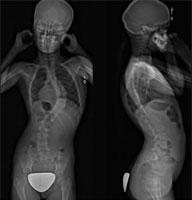

À l’aide d’implants posés sur la colonne vertébrale, la technique mise sur la croissance de l’enfant au fil des ans pour redresser sa colonne. Contrairement à la technique habituelle qui laisse une importante cicatrice dans le dos, fusionne des vertèbres et limite la liberté de mouvement, les équipements de pointe utilisés permettent d’offrir aux enfants une chirurgie non-invasive, en positionnant avec précision les implants sur la colonne vertébrale grâce à la thoracoscopie, la navigation peropératoire et le scan portable O-Arm™. L’opération dure entre quatre et six heures, les patients sont hospitalisés entre quatre et cinq jours, et le retour aux activités sportives est assez rapide, soit entre trois et quatre mois suivant la chirurgie. Il s’agit donc d’une importante avancée dans la vie des adolescents souffrant de scoliose.

Vidéo de la chirurgie (durée : 2 minutes) La vidéo présente des images de la salle d’opération, une radiographie préopératoire, une thoracoscopie (chirurgie du thorax), l’installation de l’instrumentation chirurgicale et une radiographie postopératoire.